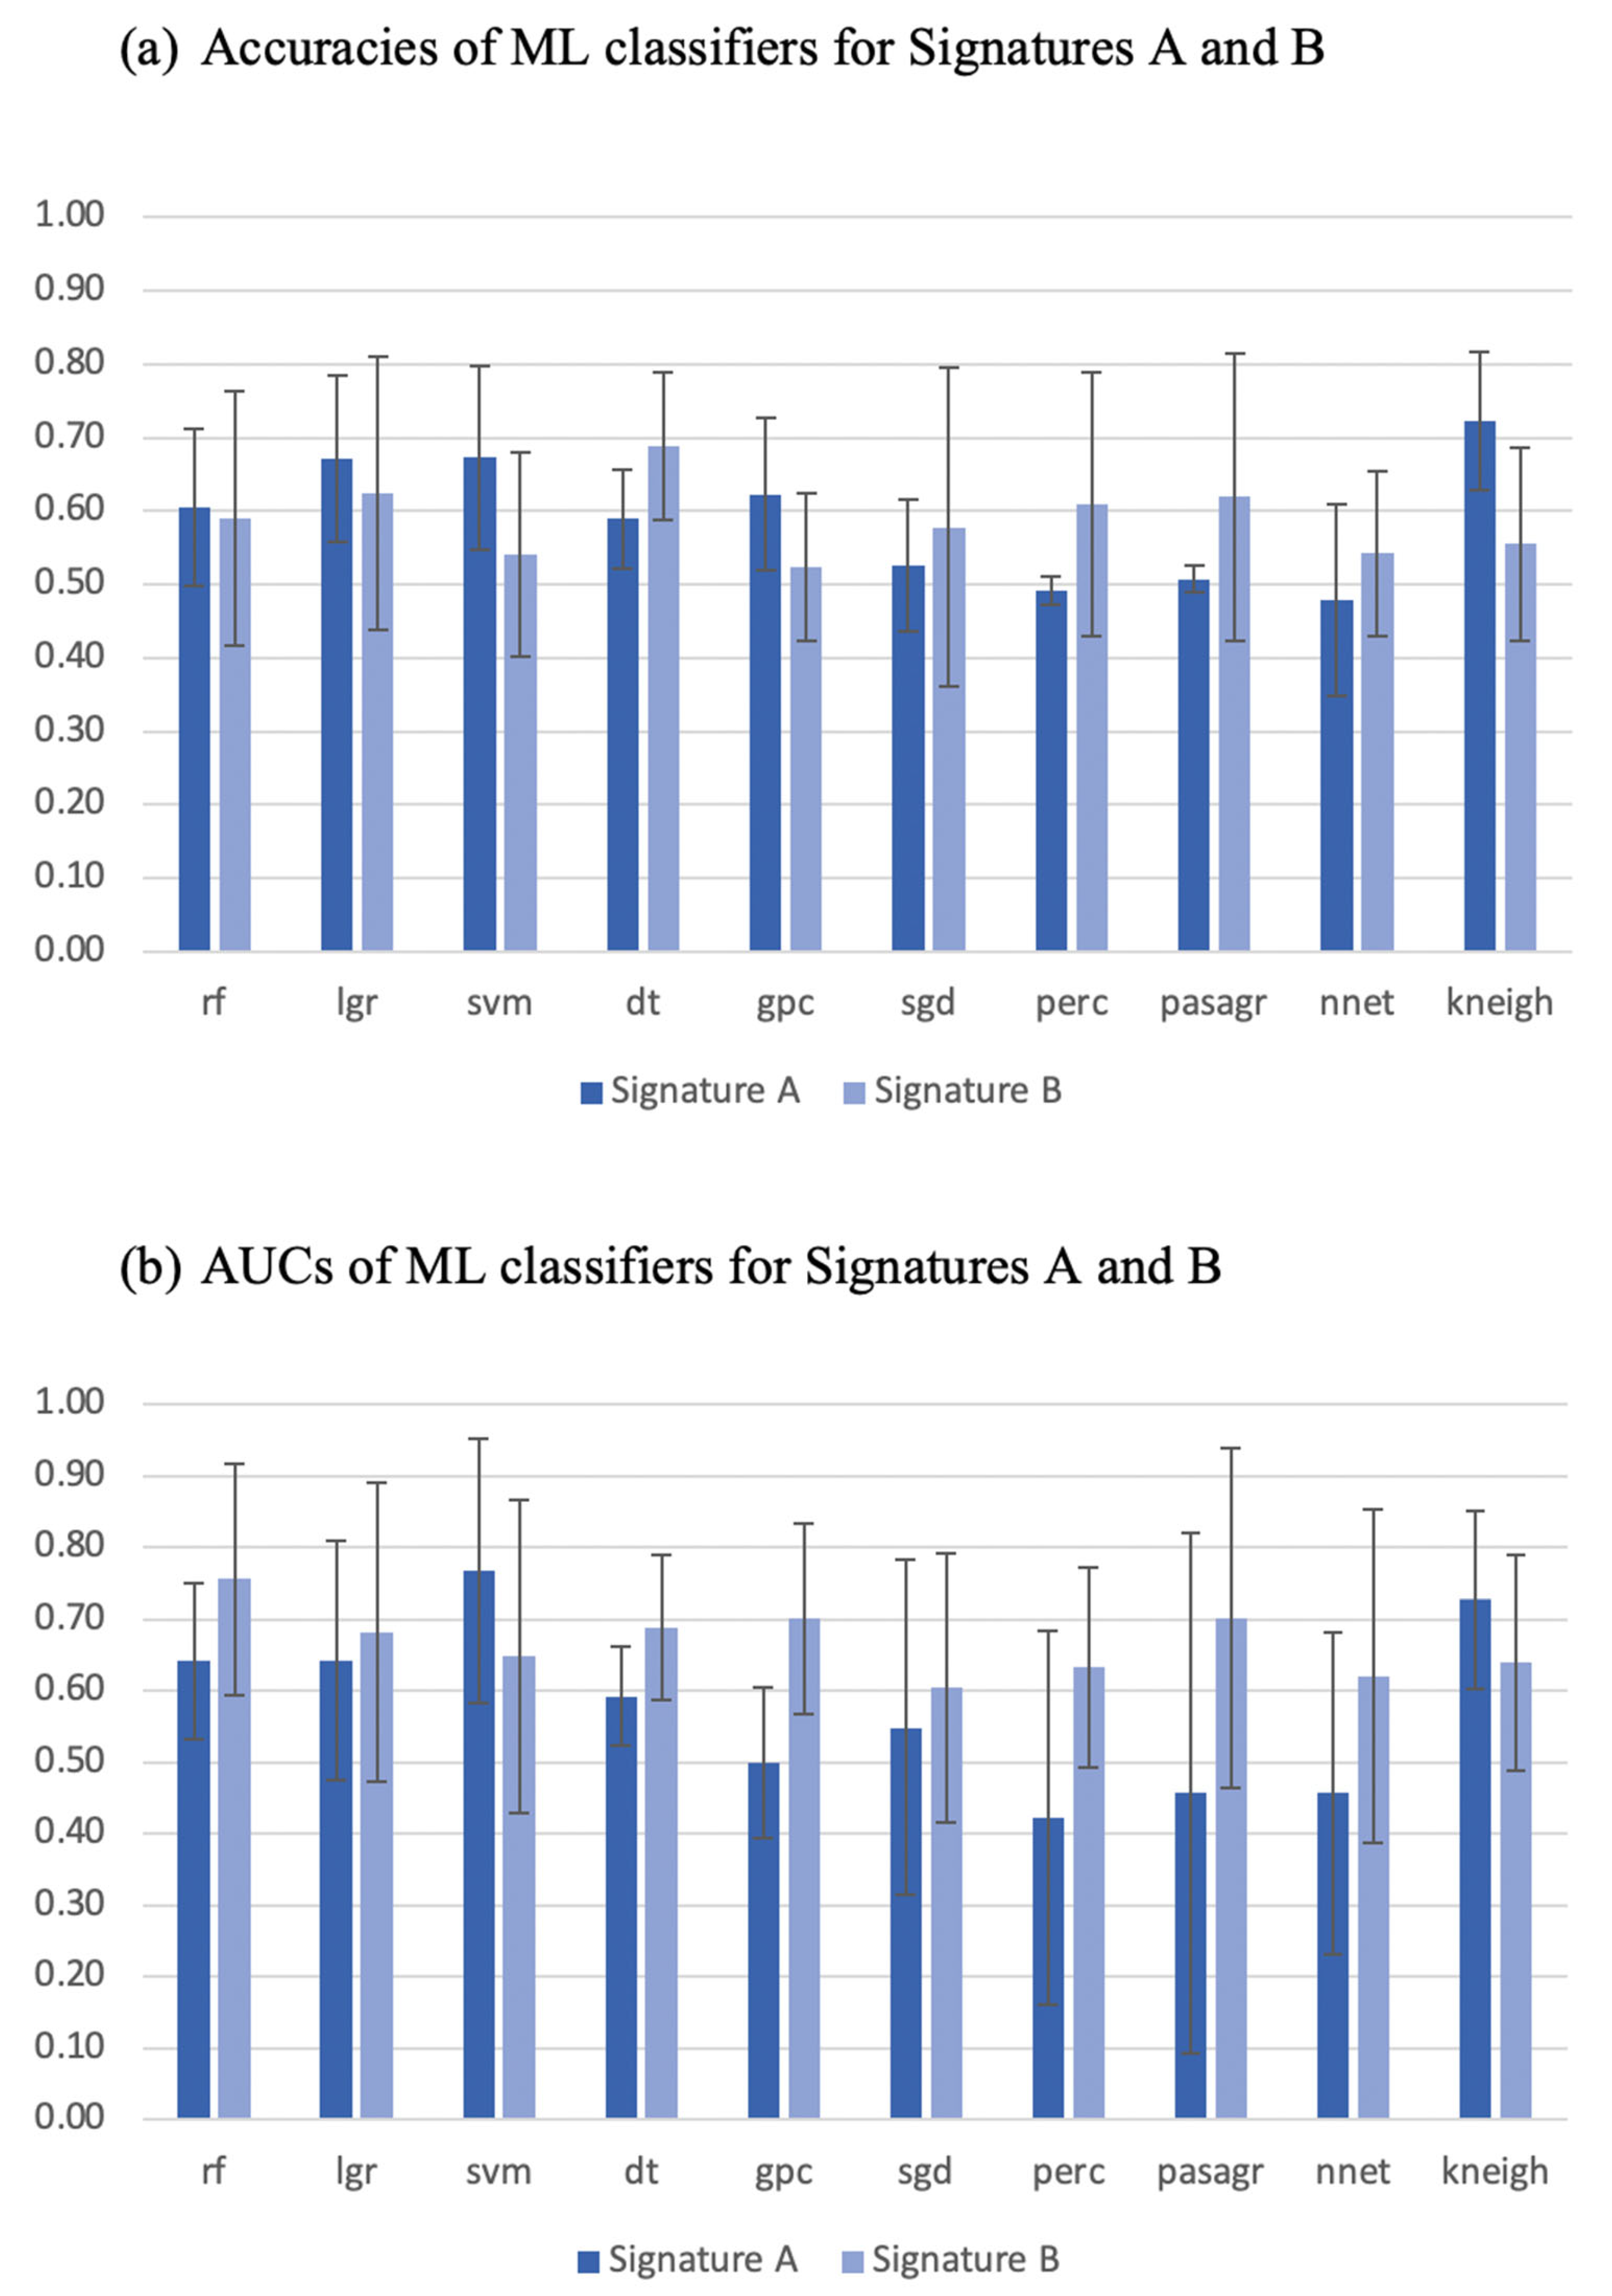

3.2. Signature Building and Machine Learning Performance